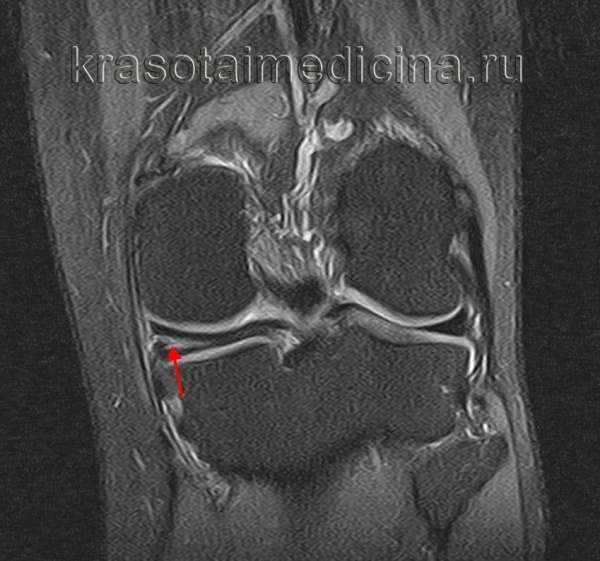

Киста менисков – это заполненная жидкостью полость в толще мениска. Протекает хронически. Основная жалоба больных с кистой мениска - боль, возникающая и усиливающаяся при движениях в суставе. При осмотре на боковой поверхности колена обнаруживается припухлость. Окончательный диагноз выставляется по данным артроскопии, УЗИ или МРТ коленного сустава. Лечение заключается в рассечении кисты или полном удалении измененного мениска. Операции обычно проводятся с использованием артроскопического оборудования.

У пациента возникают боли в области суставной щели, усиливающиеся при нагрузке на коленный сустав и исчезающие в покое. При осмотре травматолога-ортопеда выявляется плотная, болезненная при пальпации припухлость размером от 0,5 до 3 см по боковой поверхности сустава. Мелкие кисты менисков располагаются на уровне суставной щели, исчезают при сгибании и вновь появляются при разгибании колена, иногда не прощупываются. По мере увеличения кисты мениска опухолевидное образование выходит за пределы сустава и распространяется по пути наименьшего сопротивления.

Киста наружного мениска обычно возникает в средней трети наружной части мениска, реже – в области переднего или заднего рога. Киста менисков не соединяется с капсулой сустава, которая под давлением растущего опухолевидного образования постепенно истончается. Как правило, выпячивание располагается сзади от наружной боковой связки. Киста внутреннего мениска выпячивается сзади или спереди от внутренней боковой связки, реже выдается через толщу связки. Длительно существующая киста мениска вызывает дегенеративные изменения костной ткани и приводит к развитию деформирующего артроза.

В травматологии и ортопедии диагноз кисты менисков выставляется на основании клинической картины, результатов УЗИ коленного сустава, артроскопии или МРТ коленного сустава. При развитии деформирующего артроза мыщелка большеберцовой кости выявляются характерные изменения на рентгенограммах (симптом Раубера-Ткаченко).